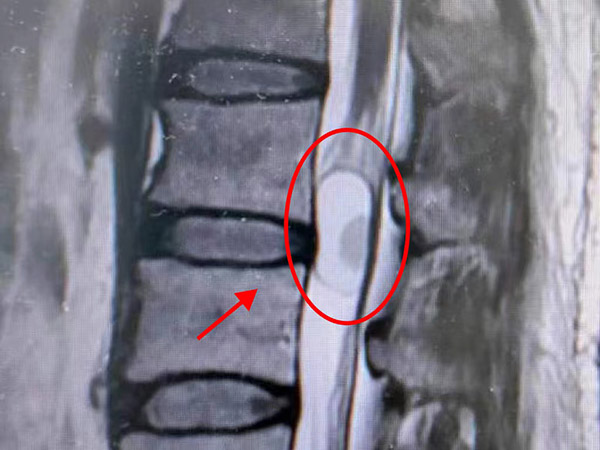

先解决燃眉之急——排尿困难。于是立即给予引流,800ml尿液被顺利引出,患者也感受到了如释重负。但医生们并没有就此停止查找病因,随着排查范围的逐渐缩小,一个大胆的猜想浮出水面“会不会是脊髓问题”,于是立即安排患者进行腰椎磁共振检查。很快,结果验证了医生的判断,患者腰1-2水平椎管内长了一个小东西,圆圆润润,鹌鹑蛋大小,中间还有一包液体。为了明确椎管内这个小东西,泌尿外科医生请来了神经外二科主任张东强前来会诊。

经过张东强详细了解病情、查体,并结合腰椎增强磁共振检查结果,考虑患者臀部麻木和排尿障碍都是这个小东西惹的祸——腰1-2椎管内肿瘤,就是这个肿瘤压迫了圆锥马尾神经,导致患者出现尿便障碍、臀部及会阴部的麻木以及右侧肢体的麻木疼痛。